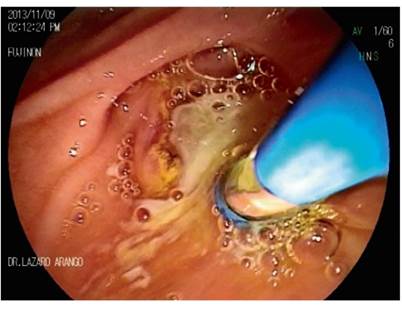

Primary pancreatic duct stones smaller than 5 mm are managed with standard ERCP maneuvers for stone removal (Figures 7, 8, 9, 10). Stones larger than 5 mm require the use electrohydraulic, extracorporeal, or Spyglass-guided electrohydraulic lithotripsy. In the latter case, the duct can be entered for use of a laser to fragment stones. 29 We have been gaining experience with the use of a cholangioscope which has been very useful for non-surgical management of patients with pancreatic stones. Figures 11, 12 and 13 show the Spyglass inside the Wirsung duct performing laser lithotripsy on a large stone. After the procedure, a pancreas stent is always placed.

Figure 7 Cannulation of the Wirsung duct. Cloudy material is seen due to chronic pancreatitis (image courtesy of the Union of Surgeons SAS, Lázaro Arango).

Figure 8 Opening cut of the pancreatic duct (image courtesy of the Union of Surgeons SAS, Lázaro Arango).